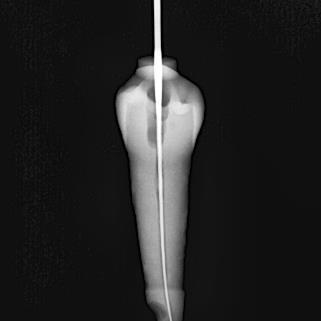

Conductometría real

Una vez que se realizó el acceso cameral de cada uno de los dientes, se procedióatomarunaradiografíaconunalima 15, finalmente se tomó una radiografía para determinar la conductometría real. (Figura 3)

Espacio Universitario. Año 4. No. 9. Octubre 2022

Figura 3.

ConductometríarealdeOD#27

Fuente: Pérez V, Salinas L. 2022